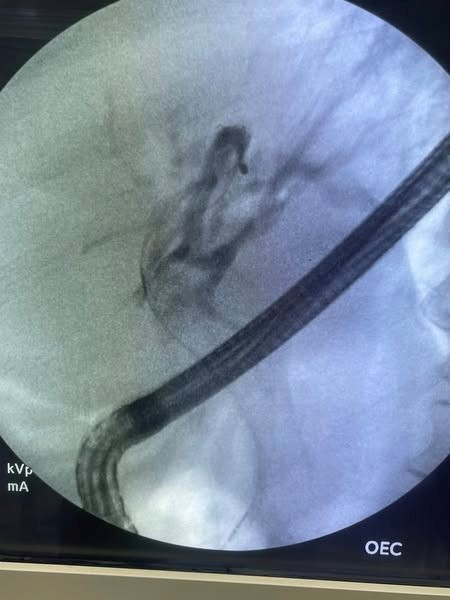

But we failed for removal and transfer the patient for surgical exploration but surgery refused exploration. Patient returned now with severe cholangitis we do ERCP and our plan to put plastic stent inside PCSEMS but the patient was lucky this time

ERCP reveale multiple stones inside stent.

Extraction was done with dormia basket and washing then we use foreign body and fluoroscopy for removal of PCMS.

Insertion of double pigtail stent with good biliary flow.

Fig 1, Fig 2, Fig 3, Fig 4, Fig 5, Fig 6

Figure 2